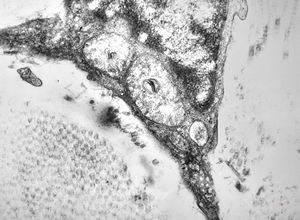

M, 2y. | globoid leukodystrophy (Krabbe disease) … n. suralis